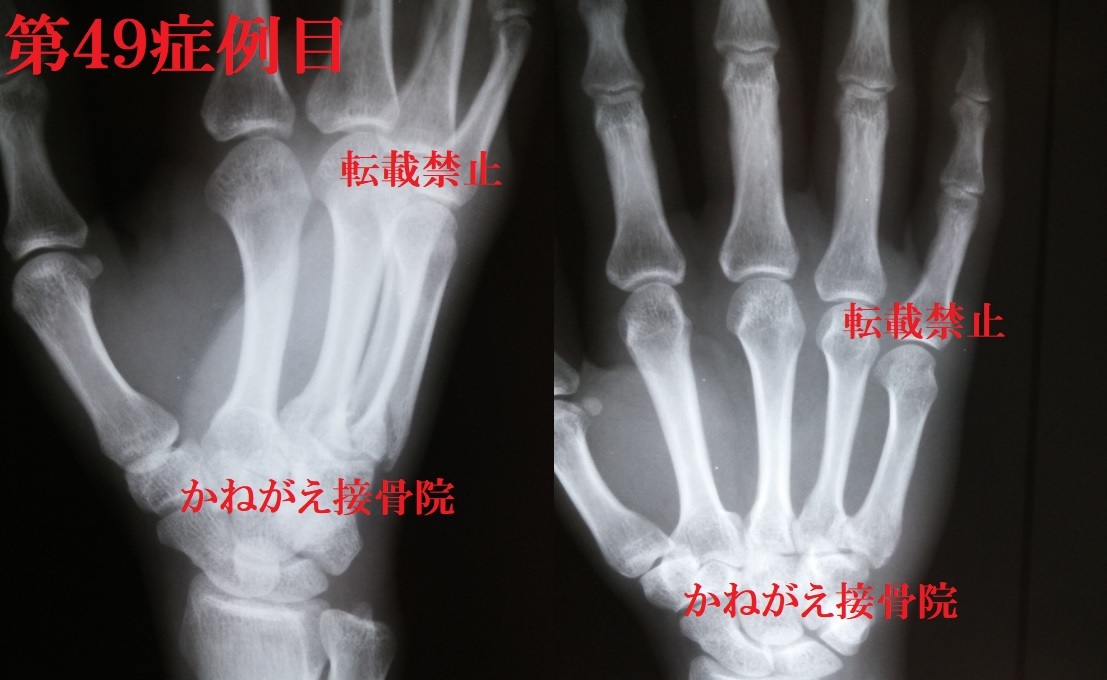

症例49

当時40歳 男性

右手第5中手骨基底部骨折

第49症例目

<当院ホームページでのみ掲載を許可された症例画像の為、無断転載はおやめください>

転位(++)→背側(+)、掌屈(+)

尺側(+)、短縮(+)

外旋(+)

第49症例目2

結果から言うと、「Repo perfect」

でした。

今回も背側転位なのに掌屈という、回転転位を伴

う症例でした。

さらに尺側転位と外旋転位があり、写真からも結

構な外旋転位であることがわかったかと思います

この場合掌屈転位は第4中手骨との位置関係でも

確認することが出来ます。

外旋転位も第5中手骨骨頭の輪郭から、度合いを

確認することができます。

整復後の写真では第4・5中手骨長軸が平行とな

り、外旋転位によって写っていた第5中手骨骨頭

の掌側傾斜の角度が外旋転位除去により減少した

ように写っていることが確認できます。

そして第5MP関節の位置が抹消に伸びているこ

とから、短縮もとれていることがわかるかと思い

ます。